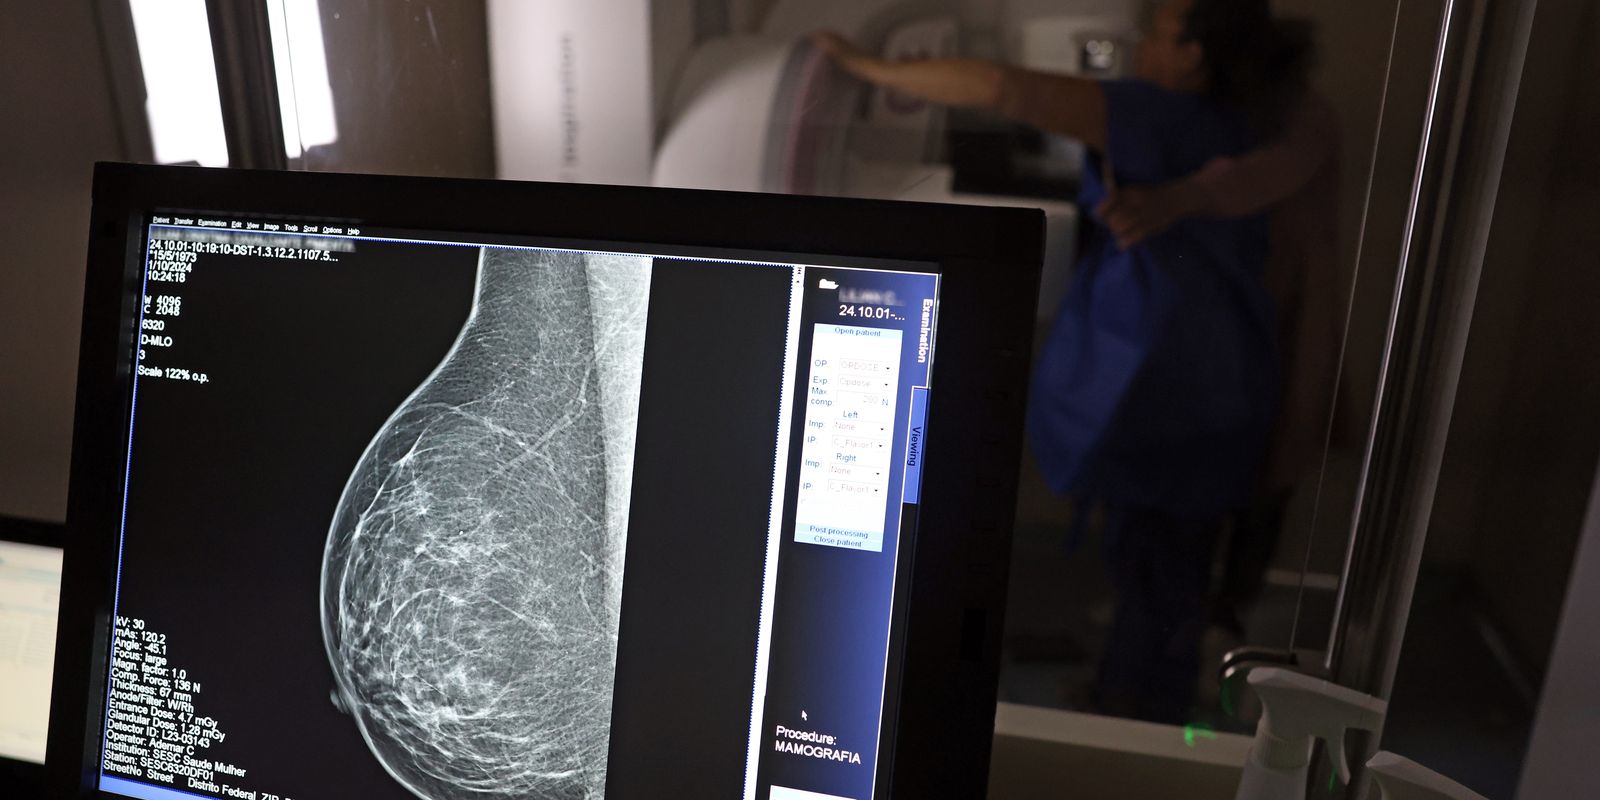

Em setembro, o Ministério da Saúde ampliou as diretrizes de rastreamento, recomendando que mulheres entre 40 e 49 anos realizem mamografias, mesmo sem sintomas. De acordo com o Instituto Nacional do Câncer (Imca), mais de 73 mil mulheres recebem o diagnóstico de câncer de mama anualmente no Brasil.

“O que é efetivo na redução da mortalidade é você descobrir o tumor antes de ter sintoma clínico. Quanto menor o tumor, melhor para a gente descobrir o tratamento e maior a chance de cura. E a gente só consegue fazer isso com exames de imagem”, diz Ivie.

Ela explica que no caso de diagnóstico de um câncer de mama com menos de 1 cm, a chance de cura é de 95% em cinco anos, independentemente se ele é do tipo mais agressivo. “E esses tumores só vão ser detectados na mamografia. Essas pessoas que têm que ir fazer mamografia são mulheres saudáveis. Não são mulheres doentes”, acrescenta.